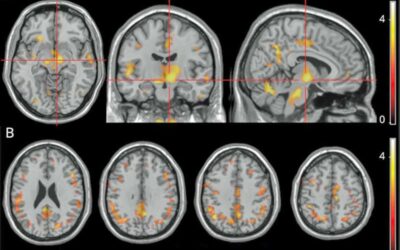

A Fatigue Nucleus in Multiple Sclerosis… and ME/CFS and Fibromyalgia?

Fatigue has been a mystery to the research world. Take multiple sclerosis (MS) – one of the most fatiguing diseases known. Fatigue is often one of the first symptoms that shows up in MS and it’s often the most troubling symptom MS patients experience, yet the fatigue in MS isn’t … Continue reading A Fatigue Nucleus in Multiple Sclerosis… and ME/CFS and Fibromyalgia?